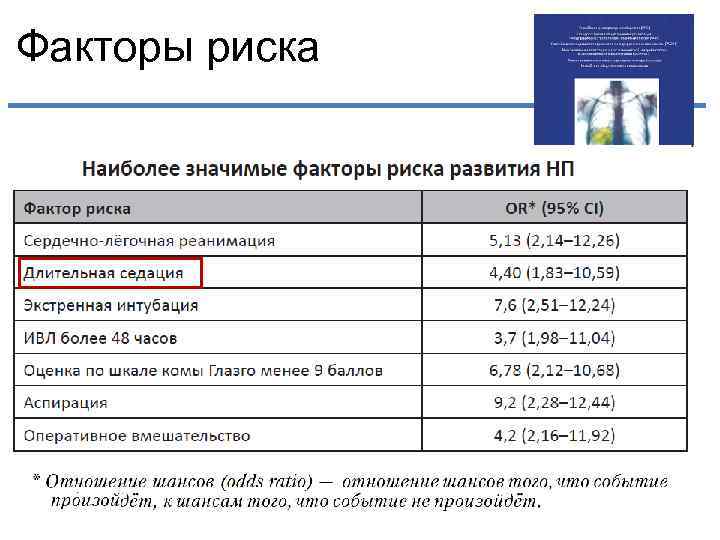

Факторы риска

Факторы риска

Факторы риска

Факторы риска